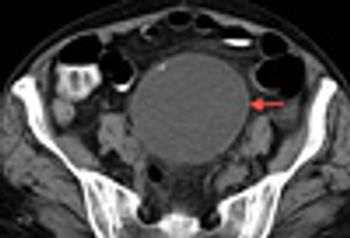

A 50-year-old African American woman with type 2 diabetes mellitus and hypertension was admitted with constant bilateral knee and thigh pain and swelling of both knees, all of 1 week’s duration. The pain was not relieved with hydrocodone/acetaminophen and had caused weakness and subsequent falls.